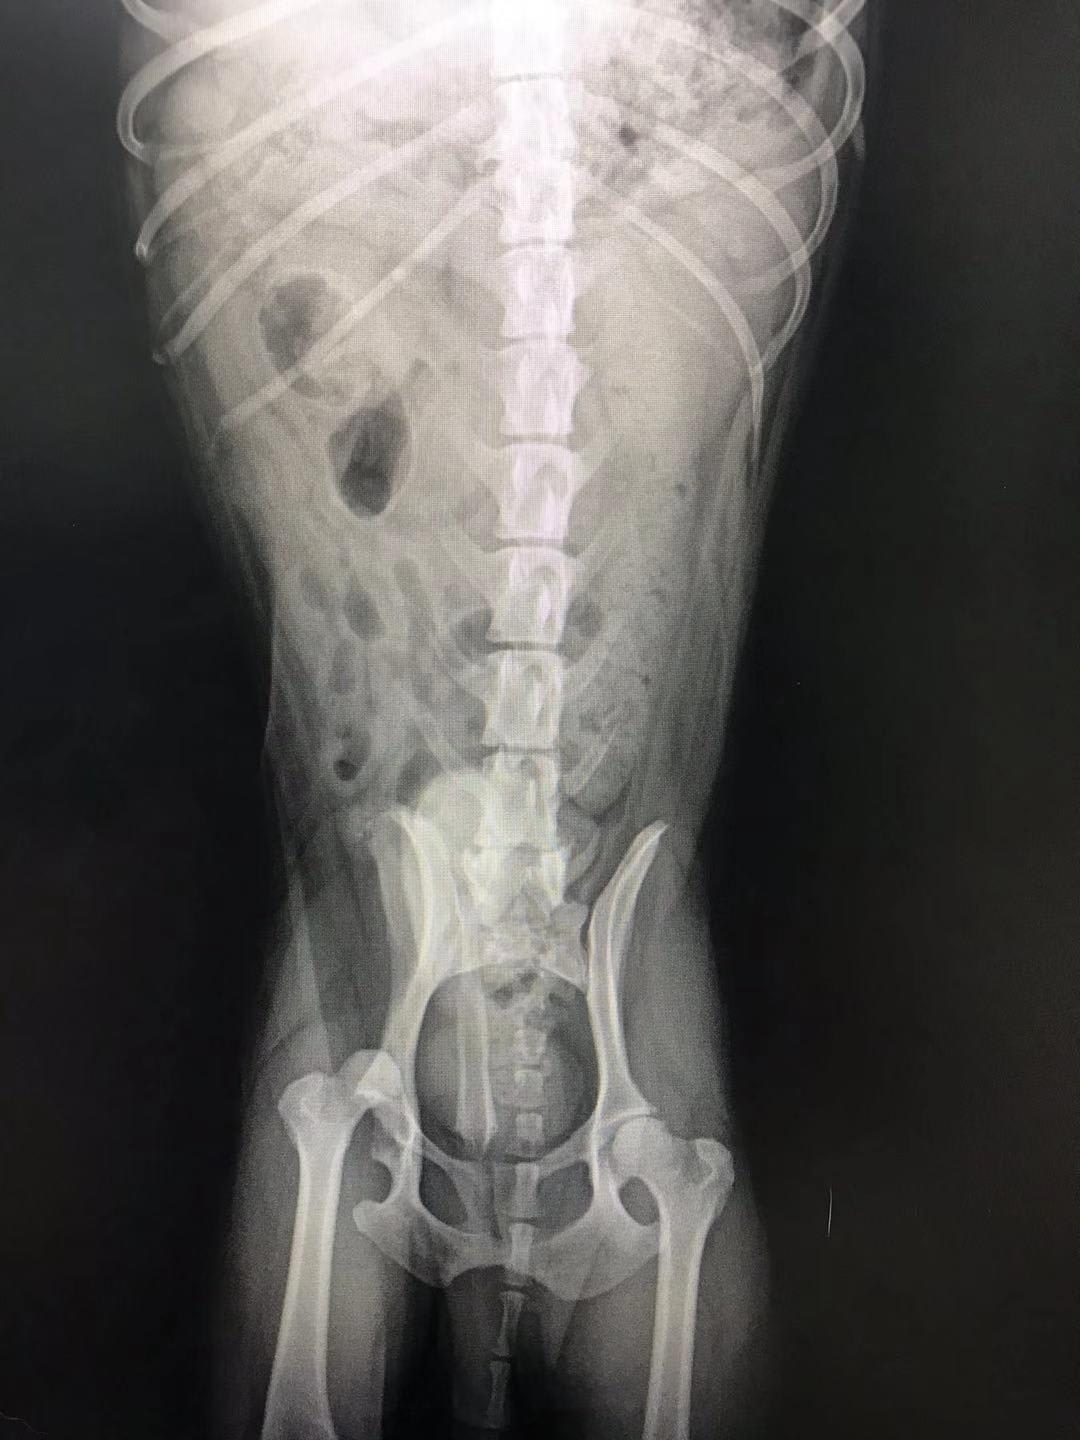

Hello, my dog is 8 years old now and he's facing two problems. The first one is patellar dislocation found two years ago and now it's the 3rd stage. Besides, he had a fight with a big dog 10 days ago, we took a X-ray today and found femoral ligament rupture. I'm wondering what treatment is best for him? Thank you very much.

Luxating patella is very common in small breed dogs. It can cause arthritis, and there is a surgery to address it if your vet tings Doudou is a good candidate. https://www.petcoach.co/article/luxating-patella/ As for the dislocated hip, he needs to surgery to replace it or to have the ball of the femur amputated (called a femoral head ostectomy - FHO). It sounds drastic, but is a very common surgery. The muscles of the hip/but will keep the joint in place, and, once healed, he should look completely normal when walking. You should discuss all available options with your vet, since the best one depends on the individual pet and their medical history. https://www.petcoach.co/article/5-most-common-orthopedic-injuries-in-dogs/